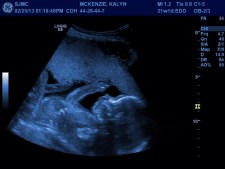

We are thrilled to be welcoming our third child to our little family this March! Much like her older sister, this little girl is already enjoying surprising mommy & daddy. While unexpected, she is very much wanted and we cannot wait to meet her!

The biggest difference in this pregnancy is that I decided to have a prenatal test done. This test would clue us in on any abnormal chromosomal activity. So effectively, we would know when I was barely 10 weeks if there was a chromosomal abnormality present. (As a big bonus, we also would learn the gender of our baby!) Every pregnancy is scary so I decided to shed some light on some of the fear so that I could begin to let go and revel in this one.

Now we still have that big, scary anatomy scan coming up in a couple of weeks. I have chosen to not care anymore. Those thoughts will come and go and eventually will fade back into the recesses of my mind where I prefer them to reside anyway. Soon we will welcome our little girl. She will meet her big sister and big brother and all will be right with our little world, no matter who she is and who she will become. ❤